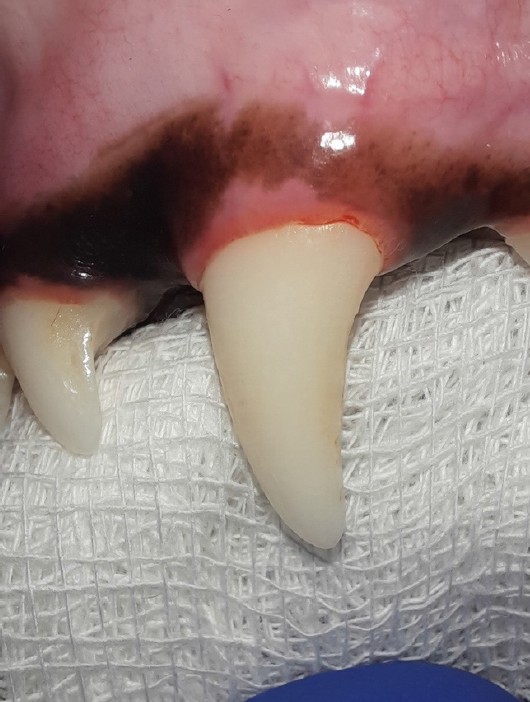

Fig. 1. Healthy gums and clean tooth (204 tooth)

Source: VTC "Dentalvet".